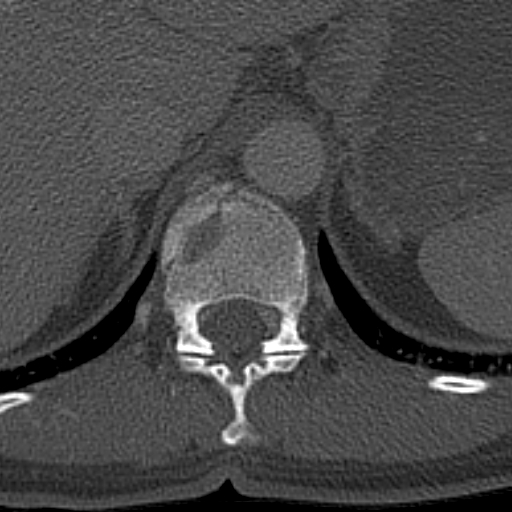

• o Because of their similar physical characteristics nephroliths (ureteroliths) can be examined the same way as gall stones. The so called renal radiography is a more direct X-ray examination of the kidney. The use of sonography can be limited by gas filled bowels. At times, only indirect signs such as pyelectasis or the segmental dilation of the ureter can be seen. In some other cases, kidney stones do not cause any urinary dilatation or congestion. “Mobile” stones are missed by the radiologists a lot more frequently – or cannot even be assessed – especially if they are in the middle segment of the ureter where they are more likely to be covered by bowel gas shadows. Juxtavesical nephroliths (if the urinary bladder is well expanded with urine) are often visible due to their acoustic shadowing. In case of uncertainty, after the initial imaging methods (or even as a primary examination) abdominal non contrast enhanced CT,a so called low dose CT examination can be performed. There are further advantages to CT or low dose CT examinations compared to other modalities. They are more objective, imaging is faster with less artefacts. Moreover, other extraurinary structures are more readily assessable (even if the lack of iv. contrast in non contrast enhanced examination has only limited value for tissue characteristics). CT can help to detect other acute processes of the differential diagnostic group.